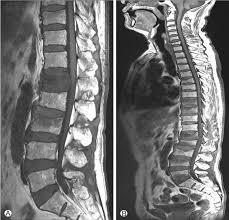

Injury To The Vertebral Endplate Disk Complex Associated With Osteoporotic Vertebral Compression Fractures American Journal Of Neuroradiology

Injury To The Vertebral Endplate Disk Complex Associated With Osteoporotic Vertebral Compression Fractures American Journal Of Neuroradiology from www.ajnr.org

Over the weekend i have been experiencing pins and needles in my right hand and arm, a sensation of someone pouring cold water on my left thigh and. The fracture line breaches both the anterior and posterior vertebral body cortex and the anterior superior endplate. A compression fracture is a type of fracture or break in your vertebrae. They often occur in the upper lumbar segments as well, such as l1. In the lumbar region, where the most axial load is, the vertebrae of level l (1 and 2) are injured. Compression fractures are the most common type of fracture affecting the spine. Compression fractures of the spine generally occur from too much pressure on the vertebral body. A compression fracture of a spine bone (vertebra) causes the bone to collapse in height. The doctor suggested bracing for three. Individuals that have been diagnosed with osteoporosis are very prone to developing small fractures in the spine, eventually leading to a compression fracture. The vertebrae are the bones in your back that are stacked on top of each other compression fractures can cause the vertebrae to collapse, making them shorter in height. Apply the one that makes the injury feel better. One and a half years back i got a compressed l1 fracture as a result of a car accident.

First, the fracture itself can cause significant pain, and media gallery. Applying heat in the first few days after an injury draws more blood to the injury site, thus. There is a 3 mm retropulsion into the spinal canal, resulting in only mild canal. Lumbar compression fractures can be a devastating injury, therefore, for 2 reasons. Compression fractures tend to heal completely in about 8 to 12 weeks. More often, the vertebra with a. Vertebral compression fractures | american association of neurological surgeons. Rarely, compression fractures occur in healthy vertebrae as a result of trauma. Anteroposterior and lateral radiographs of an l1 osteoporotic wedge compression fracture. Compression fractures of the spine usually occur at the bottom part of the thoracic spine (t11 and t12) and the first vertebra of the lumbar spine (l1). The fracture line breaches both the anterior and posterior vertebral body cortex and the anterior superior endplate. Apply the one that makes the injury feel better. A compression fracture is a type of fracture or break in your vertebrae.